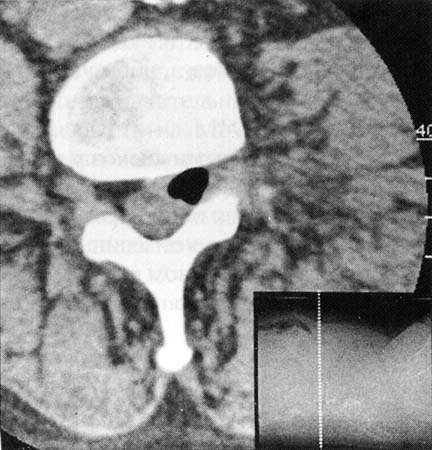

При наличии грыжи межпозвонкового диска газ может определяться в полости её при компьютерной томографии.

Больной мужчина 48 лет поступил в отделение нейрохирургии с болями в поясничном отделе позвоночника, корешковыми жалобами. Оперирован 4 года назад по поводу грыжи диска L4-5 (гемиламинэктомия L4). На обзорных снимках поясничного отдела позвоночника выявлены признаки остеохондроза, смещение тел L3, L4 кзади на 3 и 4 мм соответственно. Для исключения гипермобильности были произведены функциональные рентгенограммы в положении максимального сгибания и разгибания, на которых значительного увеличения листеза выявлено не было, отмечалось увеличение вертикальной подвижности тел позвонков (в основном в сегментах L3-4и L4-5).

Кроме того, в проекции дисков L3-4, L4-5 и L5-S1 визуализировались треугольной формы просветления газовой плотности, которые и были расценены как «вакуум-феномен» (на данной рентгенограмме газ чётко виден только в диске L3-4)

Данное наблюдение представлено всего одним случаем и имеет целью ознакомить коллег с ним воочию, так как этот эффект в практике рентгенолога встречается довольно редко.